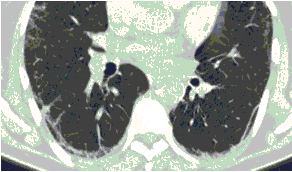

КТ имеет высокую чувствительность в выявлении изменений в легких, характерных для COVID-19. Применение КТ целесообразно для первичной оценки состояния ОГК у пациентов с тяжелыми прогрессирующими формами заболевания, а также для дифференциальной диагностики выявленных изменений и оценки динамики процесса. КТ позволяет выявить характерные изменения в легких у пациентов с COVID-19 еще до появления положительных лабораторных тестов на инфекцию с помощью МАНК. В то же время, КТ выявляет изменения легких у значительного числа пациентов с бессимптомной и легкой формами заболевания, которым не требуется госпитализация. Результаты КТ в этих случаях не влияют на тактику лечения и прогноз заболевания при наличии лабораторного подтверждения COVID-19. Поэтому массовое применение КТ для скрининга асимптомных и легких форм болезни не рекомендуется. При первичном обращении пациента с подозрением на COVID-19 рекомендуется назначать КТ только при наличии клинических и инструментальных признаков дыхательной недостаточности (SpO2 < 95%, ЧДД > 22).

3. Применение лучевых методов у пациентов с симптомами ОРВИ легкой степени тяжести и стабильном состоянии пациента, возможно только по конкретным клиническим показаниям, в том числе при наличии факторов риска, при условии достаточных технических и организационных возможностей. Методом выбора в этом случае является КТ легких по стандартному протоколу без внутривенного контрастирования или РГ при ограниченной доступности КТ. Использование УЗИ в этих случаях нецелесообразно. Применение КТ исследования в сроки ранее 3 - 5 дней с момента появления симптомов заболевания, а также при отсутствии клинических проявлений поражения бронхолегочной системы является нецелесообразным. Выполнение КТ целесообразно при наличии клинических и инструментальных признаков дыхательной недостаточности (SpO2 < 95%, ЧДД > 22), либо при дифференциальной диагностике с другим заболеванием.